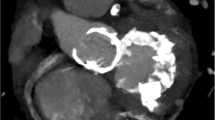

MAC can be visualized and quantified from a single computed tomography (CT) image acquisition (Fig. 4) without additional contrast agents [41]. Electrocardiogram (ECG)-gated cardiac CT is a useful tool to measure the extent and location of MAC and to plan the surgery when indicated. It can accurately show areas where there is more calcium, where it does not allow suture, and where it is safe to do. It can also predict the need for decalcification and reconstruction of the annulus, providing vital anatomical information reducing periprocedural risk of complications [21, 42]. In patients undergoing transcatheter mitral valve replacement (TMVR), cardiac CT is crucial to evaluate the left ventricle outflow tract (LVOT) to predict obstruction after valve implantation [43•].

CT for the evaluation of MAC should ideally have high-resolution images of the left atrium (LA)–left ventricle (LV) annular junction, to clearly assess the full extent of the disease, which in some cases can infiltrate the LV, interventricular septum, and right ventricle.

Due to its pattern, some areas of the annulus that may appear to be heavily calcified in CT scan are in truth fibrotic tissue [44].